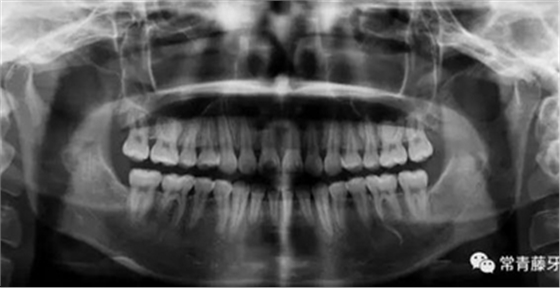

影像學(xué)檢查

曲斷顯示38、48阻生;雙側(cè)TMJ髁突頭略不對(duì)稱(chēng)。

頭影測(cè)量顯示上下頜骨發(fā)育不足,且呈現(xiàn)骨性Ⅱ類(lèi)。

曲斷可見(jiàn)牙根基本平行。